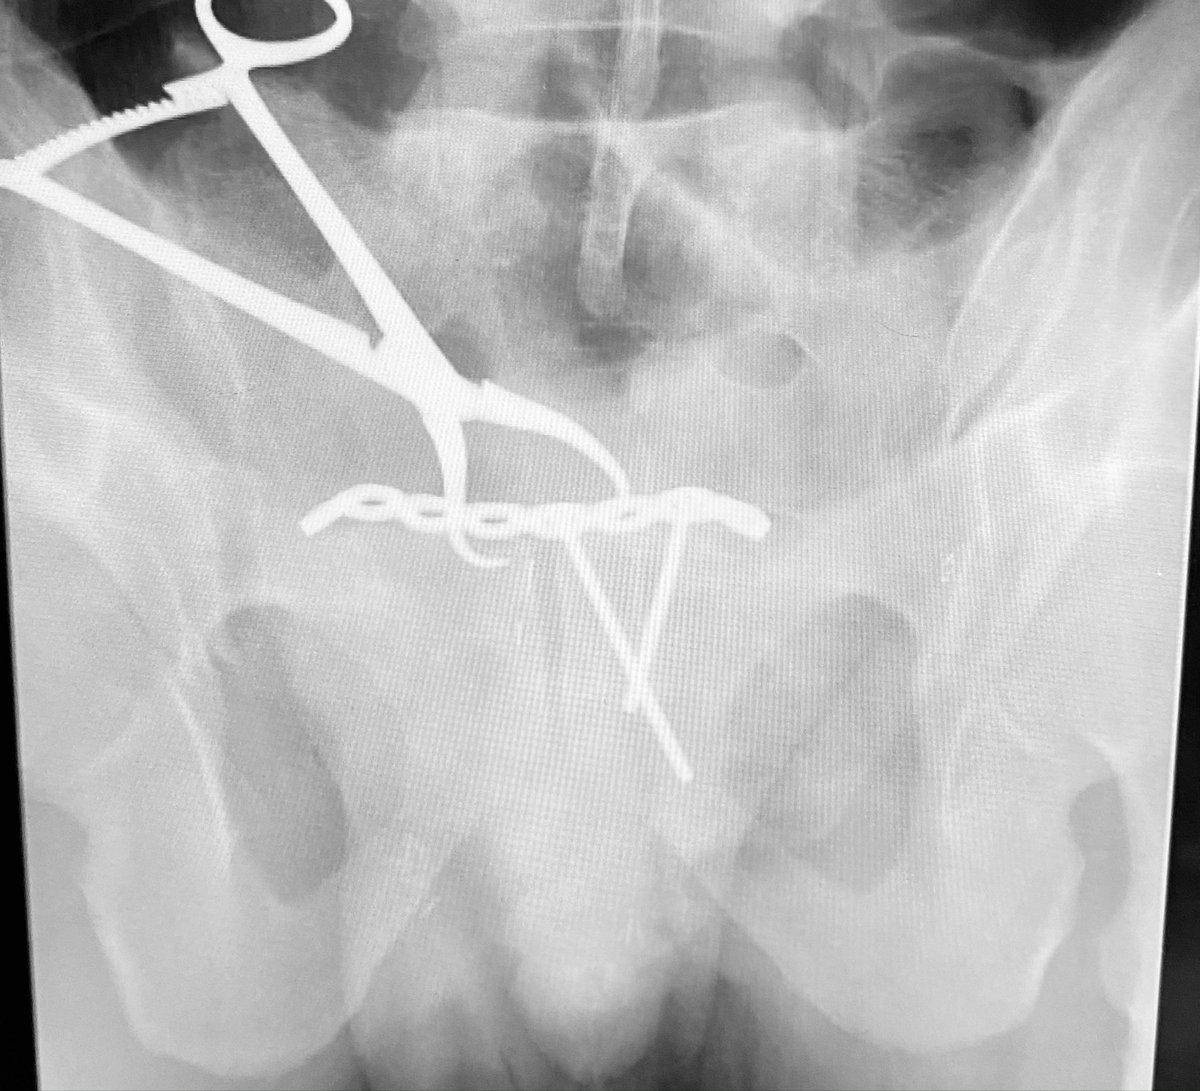

What will you do for this 50yo active male with an isolated closed pelvic ring injury? He was injured 2 days ago and has been HD stable and neuro normal since injury.

With the patient positioned supine, his pelvic region elevated 2-3” on a soft sacral midline support of folded blankets, in 15# of right distal femoral traction, and fully relaxed under GA, this is the right hemipelvic displacement and deformity - how do you use this info?

The vector of the tenaculum clamp needed to correct the deformity obstructed plating. So we contoured and secured the plate on the left side and then applied the reduction clamp again vectored as necessary to achieve and maintain the reduction

Another view to show the plate and clamp locations